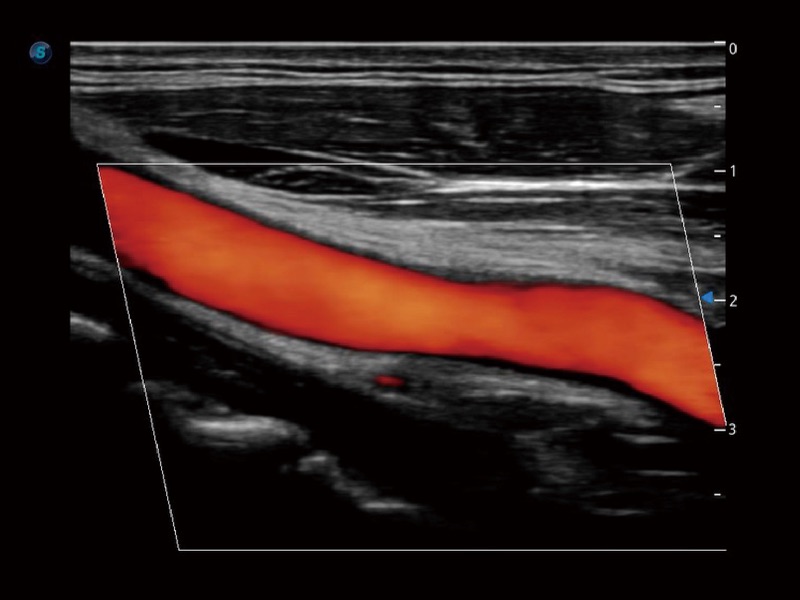

• 血管内中膜自动测量 Auto IMT

血管内中膜的厚度值是预测心血管疾病风险的重要指标,Auto IMT可以实现血管近场和远场内中膜厚度的自动测量,为临床提供快捷有效的诊断工具。

临床图